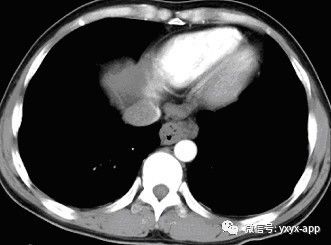

CT增强动脉期

【影像表现】X线吞钡:食管下段迂曲,管壁呈锯齿状改变,粘膜皱襞增宽、增粗,扭曲呈蚯蚓状,并可见串珠状充盈缺损,食管稍扩张,管壁轮廓凹凸不平,钡剂排空延迟。管壁柔软,舒缩功能良好。 CT平扫及增强扫描可见食管内多发类圆形稍低密度病灶,动脉期未见明显强化,门脉期强化明显,与同层面主动脉强化程度相仿,显示病灶为血管性病变。肝脏大小比例失调,肝表面结节样不平,肝内密度尚均匀,未见明显局灶性密度异常及异常强化。

CT:增强三维重建可以明确曲张的范围及程度,尤其对食管旁静脉曲张及静脉曲张硬化治疗后随访有一定价值。影像表现为管壁增厚,管腔不规则,常合并胃底静脉曲张,除食管黏膜下或食管旁区外,肝胃韧带区可以出现卵圆形或葡萄状软组织影,增强扫描可以显示明显强化的迂曲血管团,呈持续强化,延迟性强化。